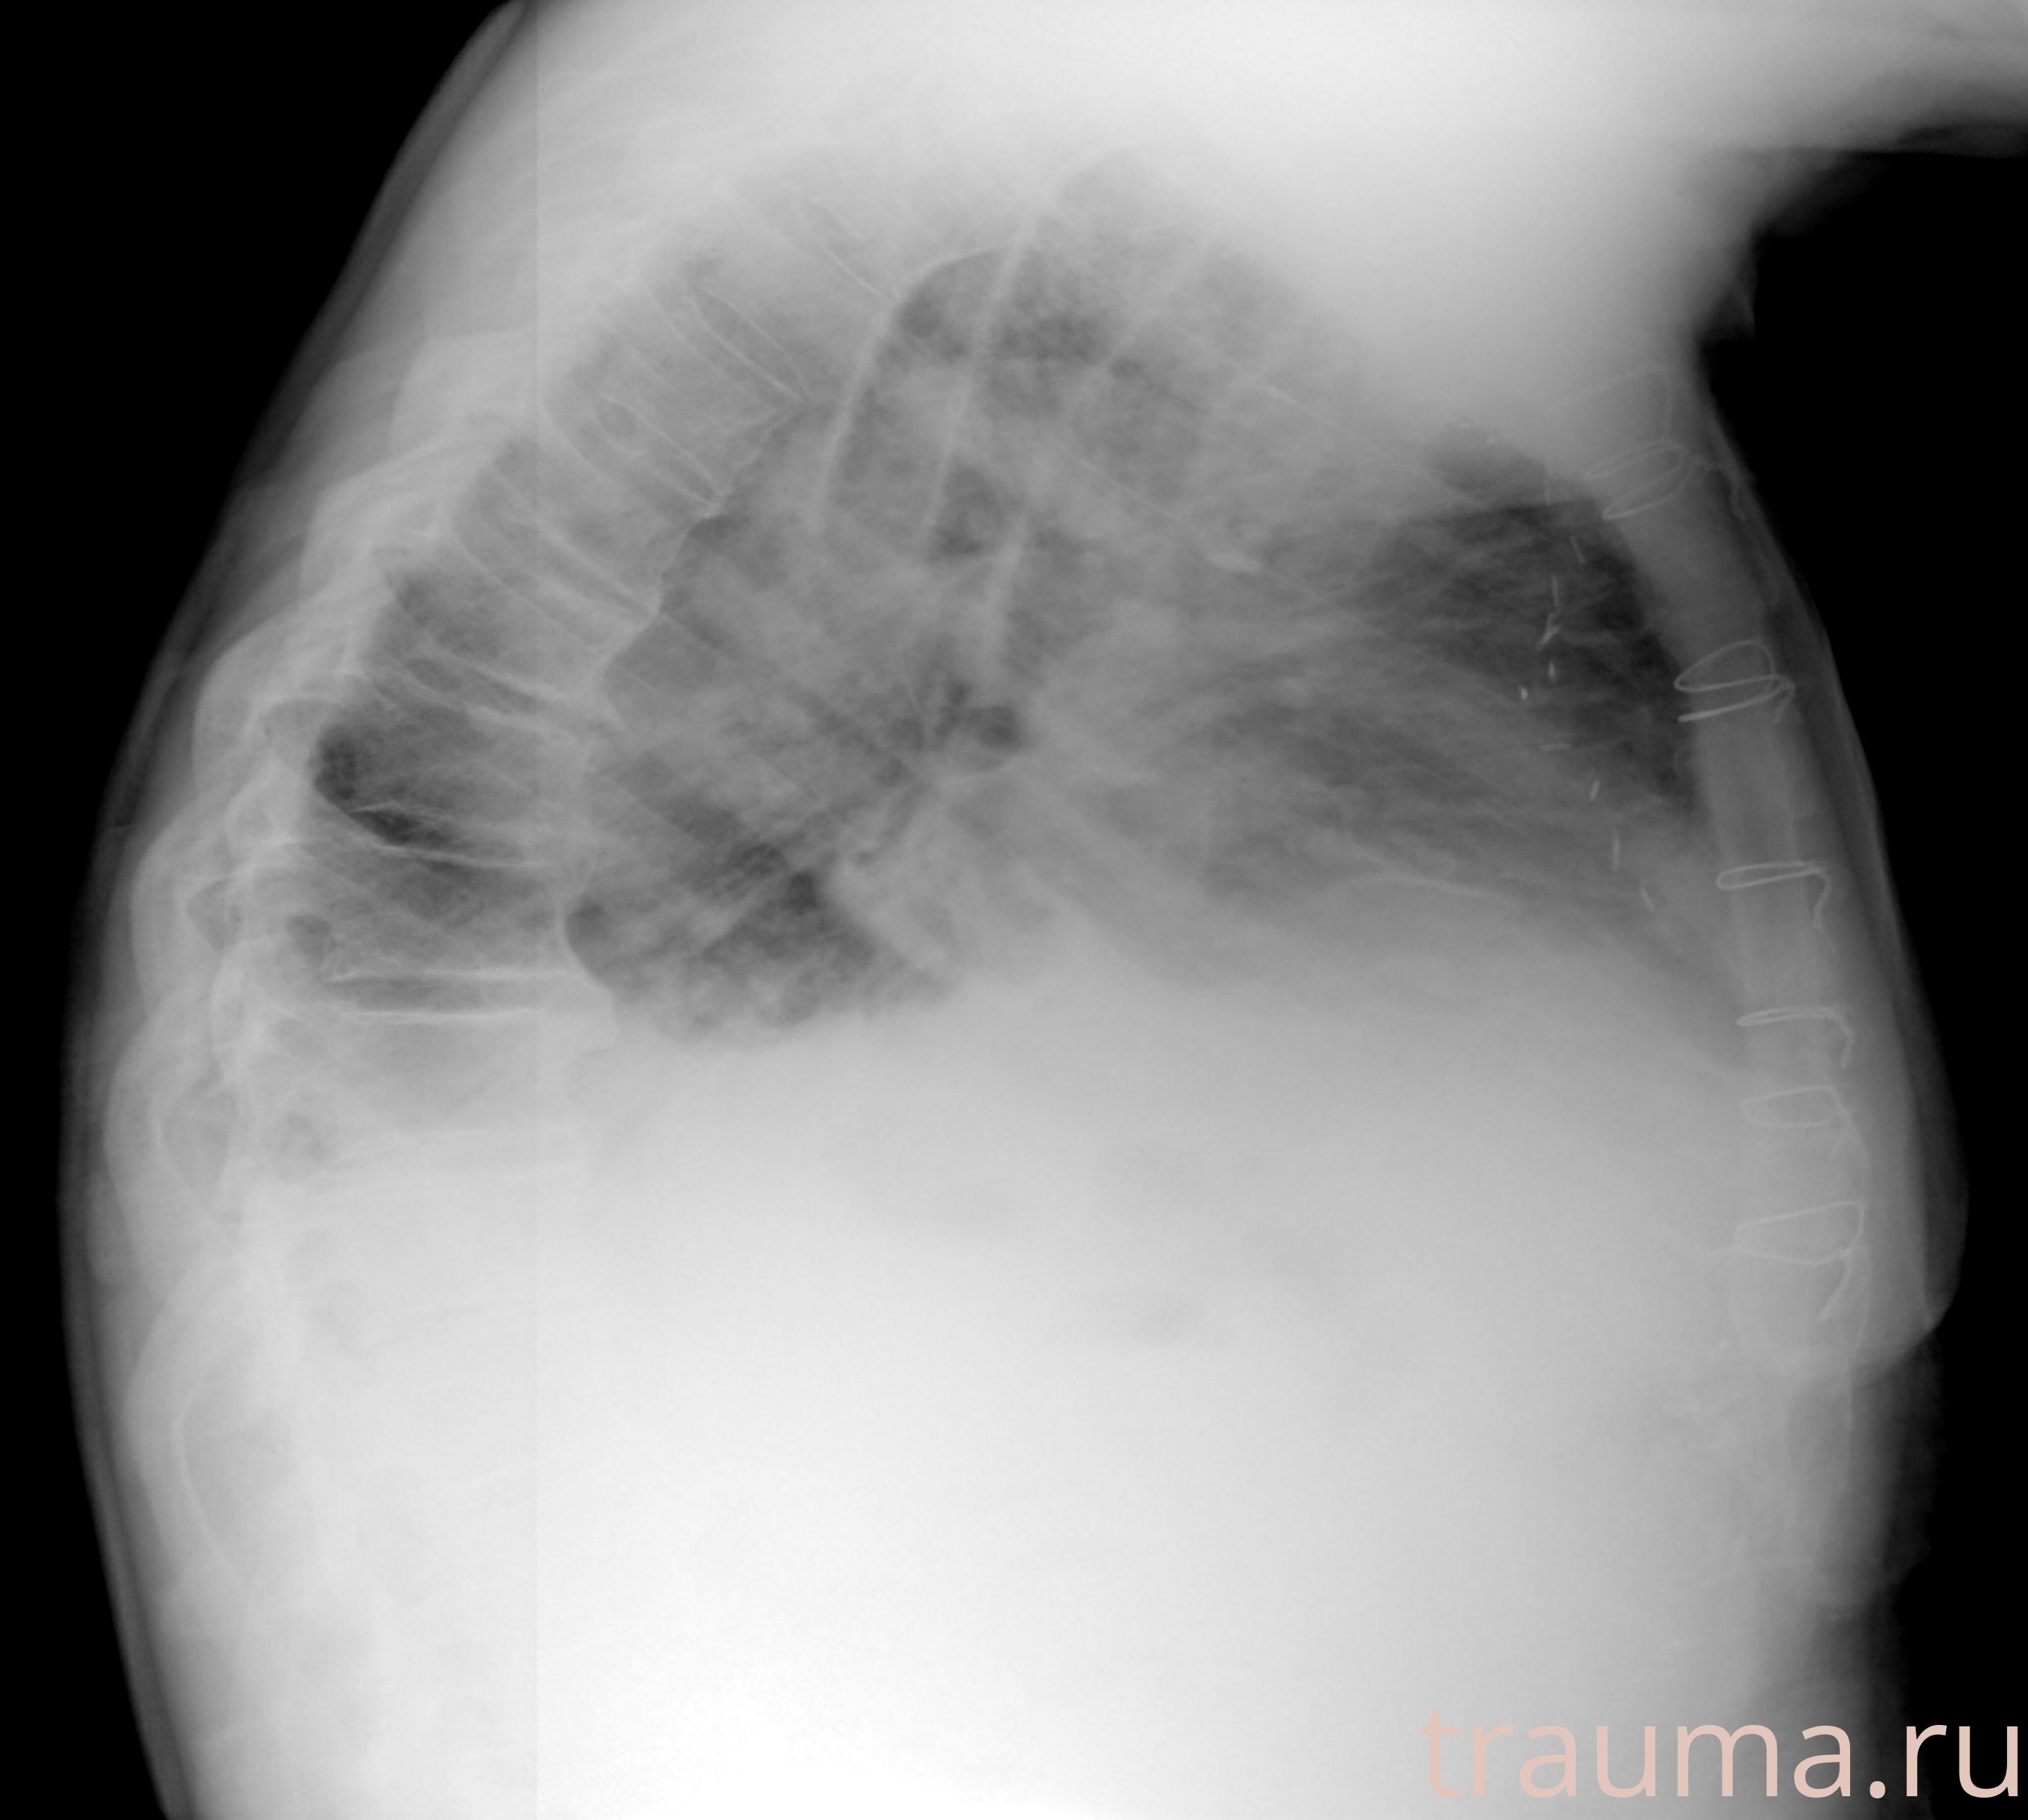

Рентген на дому: по вашему адресу приезжает врач-рентгенолог, травматолог-ортопед с мобильным рентгеновским аппаратом, проводит диагностику травмы или заболевания, делает необходимые рентгенограммы, дает рекомендации по дальнейшему лечению. Получить качественные снимки в домашних условиях возможно благодаря уникальной методике, разработанной МосРентген Центром для института  Склифосовского